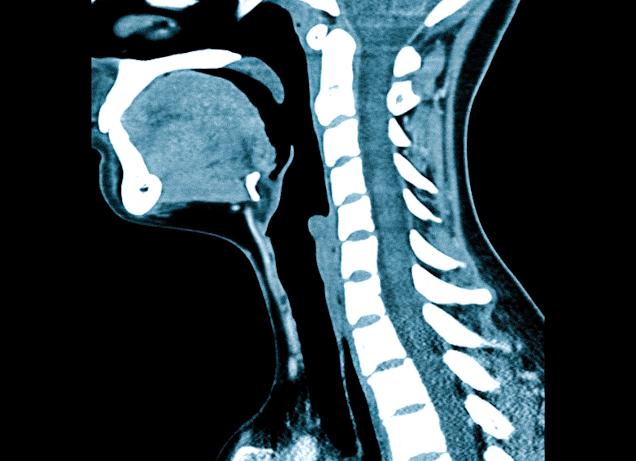

КТ мягких тканей шеи и лица — что показывает, назначение, проведение, противопоказания

Практически каждый человек за свою жизнь сталкивается с огромным количеством недугов, омрачающих её тем или иным образом. Важно стараться минимизировать негативное воздействие заболеваний, а для этого требуется внимательно следить за своим здоровьем и при появлении каких-либо нарушений или даже изменений, не имеющих очевидных причин, стоит обращаться к квалифицированным специалистам, ведь только они способны принять грамотное решение и правильно поставить диагноз, а ведь без этого невозможно даже приступить к лечению. На этом этапе многое зависит от того, насколько быстро вы начнёте терапию. Для этого необходимо использовать различные диагностические методы, например, КТ мягких тканей шеи, давайте подробнее рассмотрим это исследование в данном материале.

В процессе специальные датчики будут заниматься послойным сканированием шеи, а снимки будут поступать на компьютер специалиста. Стоит отметить и то, что они будут располагаться в разных плоскостях, что позволит максимально досконально изучить область и точно поставить диагноз.